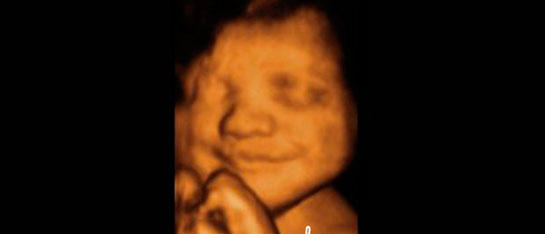

24 Haftalık Gebelik 24 haftalık gebelik, bir hamilelik sürecinin ikinci trimesterinin sonlarına yaklaşan bir dönemi temsil eder. Bu dönem, hem anne hem de bebek açısından önemli fizyolojik değişimlerin yaşandığı bir süreçtir. Bu yazıda, 24 haftalık gebelik döneminde meydana gelen gelişmeler, sağlık önerileri ve dikkat edilmesi gereken noktalar detaylı bir şekilde ele alınacaktır. Fetal Gelişim 24 haftalık gebelikte fetusun gelişimi önemli bir aşamaya ulaşmıştır. Bu dönemde, fetusun boyu yaklaşık 30 cm, ağırlığı ise 600-700 gram civarındadır. Aşağıda, fetal gelişim ile ilgili bazı önemli noktalar belirtilmiştir:

Bebek Gelişimi

Merhaba Seden, 24. hafta gebelikte bebeğinizin gelişimi gerçekten de çok heyecan verici. Bebeğinizin 615 gram civarında olması ve sesleri duymaya başlaması, bağ kurma sürecinin de başlangıcı anlamına geliyor.